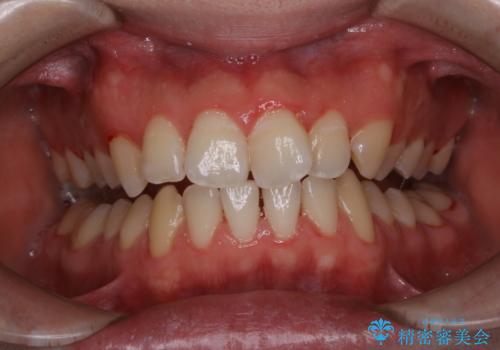

- 今まで歯医者で、クリーニングを受けたことがないため綺麗にしたいとのことでした。PMTC60分コースを行いました。

PMTCの注意事項(リスク・副作用など)

- 歯を白くする目的の施術ではありません

- 保険適用外となります